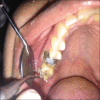

Purpose of the study: The purpose of the study is to evaluate the efficacy of three gingival retraction systems such as polyvinyl siloxane foam retraction system (magic foam cord; Coltene/WhaledentInc), polysiloxane paste retraction system (GingiTrac; Centrix), and aluminum chloride impregnated twisted retraction cord (Stay-Put; Roeko) in endodontically treated teeth.

Materials and methods: Patients who were endodontically treated for molars and requiring crown for the same, were selected for the present study with sample size of 45. The 45 participants were divided into three groups. Group 1 was treated with Stay-Put, Group 2 with Magic Foam, and Group 3 with GingiTrac. About 90 elastomeric impressions of the participants were taken-45 impressions before retraction and 45 impressions after retraction. The sulcus width was measured on the die obtained from the elastomeric impressions by placing the dies under OVI-200 optical microscope in combination with X soft imaging system software attached to a computer.